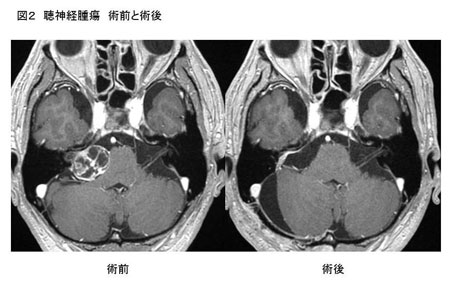

良性の腫瘍ですから、手術により腫瘍をすべて取り除く、つまり全摘出することにより、再発もなく治ります。腫瘍が大きな場合は、腫瘍の全摘出が難しくなり、手術による合併症をおこす頻度も多くなります。顔面神経は特に重要であり、術中モニタリングを行い、神経機能を温存しつつ腫瘍を摘出します(図2)。